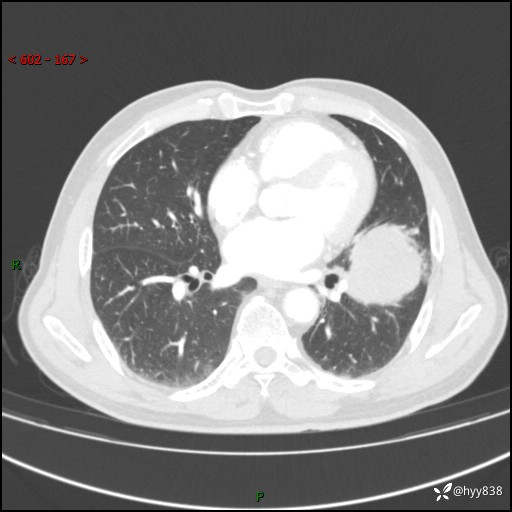

68岁/男,发现左下肺占位5天。如此大的肿块,患者竟然没有症状---结果公布~

【患者信息】:68岁/男

【主诉】:检查发现左下肺占位5天。

【现病史及既往史】:患者于4天前外院行“经尿道钬激光碎石术”,住院期间胸部CT检查发现左下肺肿块,患者平素无明显咳嗽咳痰,无心慌、胸闷、胸痛、呼吸困难、低热、盗汗,无头痛、头晕,无腹痛、腹胀等不适,现患者为求进一步治疗,遂来我院就诊,以“左下肺肿块”收入我科。 患者自起病以来,精神可,睡眠可,饮食可,大小便正常,体重无明显改变。

【检查】:胸部CT增强扫描